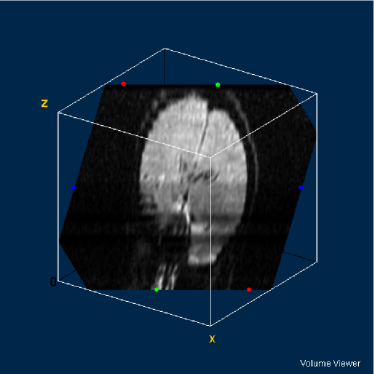

Refer to caption

Figure 15: Ground truth volume generated by polynomial net classification

To implement the proposed and used methods and rebuild volumes, we developed AnImed, a computational tool build using Object Pascal and Delphi 5 IDE. The volumes of interest were visualized using ImageJ, a Java-based tool developed by NIH (National Institute of Health, USA) and plugin VolumeViewer.